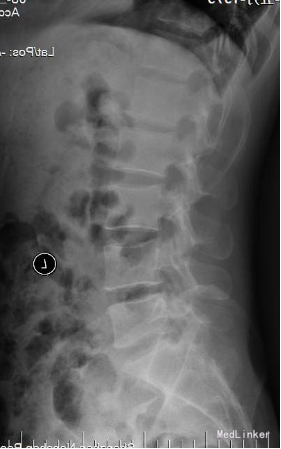

35岁 男性 主诉:反复右下肢放射性疼痛麻木8个月,加重3天

生命体征平稳,痛苦表情, 专科查体: 右下肢强迫性屈髋屈膝位; L5/S1棘突间及右侧椎旁压痛,并向右下肢放射; 右小腿后侧及足背外侧皮肤感觉减弱; 右足拇跖屈肌力3级; 右侧直腿抬高试验5°(+), 右侧跟腱反射消失。 入院三大常规,生化指标等均正常范围

诊断:腰椎间盘突出症 (腰5/骶1髓核游离型) VAS评分:9分 ODI评分:96% 疼痛剧烈,右下肢难以伸直,坐卧不宁;给予常规脱水,激素,止痛等治疗无效;不同意手术,反复要求保守治疗。 保守治疗3天,患者疼痛仍无明显缓解,同意行手术治疗 手术方案:椎板间隙入路PELD 术后予以止痛,脱水,小剂量激素等治疗, 术后第二天:右下肢麻木疼痛明显缓解。查体:右小腿后侧及足背外侧皮肤触觉恢复;右足拇跖屈肌力4+级;右侧直腿抬高试验(-);右侧跟腱反射仍减弱。 术后第5天:出现右小腿及足底针刺样疼痛症状加重,麻木感,伴有右下肢间歇性抽搐,次数较频繁,以夜间为甚。查体:腰椎活动无明显受限,右小腿后面及右足背外侧触痛明显;双下肢屈伸肌力、肌张力基本正常;右侧直腿抬高试验(-),右侧跟腱反射仍减弱。 予以加大NSAID及地米治疗,效果不明显,夜间疼痛难以入睡。复查腰椎MRI,未见髓核再脱出,减压彻底 诊断:考虑右侧骶1神经根神经病理性疼痛 治疗: 普瑞巴林 75mg Bid;神经妥乐平 2# Bid; 阿米替林 25mg Bid 外加神经营养治疗 治疗1周后,症状明显缓解